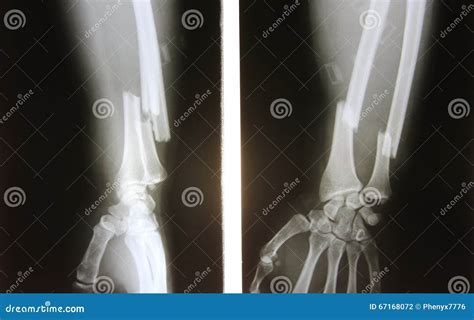

A forearm X-ray is one of the most common diagnostic imaging procedures performed in emergency departments, urgent care centers, and orthopedic clinics. Whether you have suffered a sudden fall, a sports-related injury, or are experiencing unexplained chronic pain, this imaging tool provides doctors with a vital, non-invasive look beneath the skin. By utilizing small amounts of electromagnetic radiation to create images of the bones in the forearm—specifically the radius and the ulna—medical professionals can accurately diagnose fractures, dislocations, and various other structural abnormalities. Understanding the procedure, why it is requested, and what the results mean can help demystify the process and prepare you for your visit to the radiology department.

Anteroposterior (AP) View The arm is flat on the table, palm facing up, providing a front-to-back view of the radius and ulna.

Lateral View The arm is turned 90 degrees, showing the side profile of the bones to check for displacement or angling.

• Fractures: Whether the bone is broken completely, partially (a hairline fracture), or fragmented (comminuted fracture).

• Alignment: Checking if the broken ends of the bone are touching or if they have shifted.

• Dislocations: Ensuring the bones of the elbow and wrist remain properly seated in their joints.